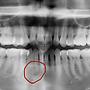

[問題] 牙齦瘤?牙齦囊腫?求解(有圖)

[ teeth_salon ]26 留言, 推噓總分: +11

作者: dontknow - 發表於 2022/05/25 16:08(3年前)

19Flog926: 推薦台大口外李正哲醫師05/27 14:52